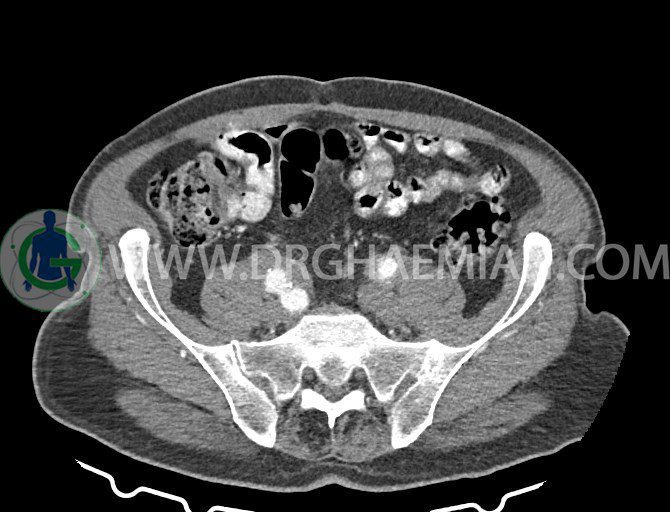

سی تی اسکن لگن یکی از روش های تصویربرداری با سی تی اسکن است. این روش با استفاده از تشعشعات تصاویر عرضی از ناحیه شکمی ایجاد میکند. در این کیس ديورتيكولوزيس، کیست های کورتیکال در هر دو کلیه، لنفادنوپاتی، کلسیفیکاسیون دیواره آئورت و شریان ایلیاک، تغییرات DJD ناحیه توراکولومبار و پروستات بزرگتر از عادی دیده می شود.

در سي تي اسکن اسپيرال شکم و لگن با و بدون کنتراست خوراکی و وريدی (مولتي ديدکتور 16 با مقاطع ظريف و بازسازي هاي ساژيتال و کرونال):

– کيست هاي کورتيکال ساده به قطر 5 mm تا 50 mm در کليه راست و به قطر 5mm تا 55 mm در کليه چپ

– کلسيفيکاسيون ديواره آئورت و شريان ها ايلياک همراه با نشانه هاي ترومبوز مورال در بيفورکاسيون ائورت با امتداد به پروگزيمال هاي شريان هاي ايلياک

– ديورتيكولوزيس در کولون نزولي وسيگموئيد

لنفادنوپاتي به ابعاد mm 22 x 25 مجاور شريان ايلياک خارجي چپ و به ابعاد mm 17 x 28 مجاور شريان ايلياک خارجي راست

– پروستات به ابعاد mm 45 x 54، بزرگ تر از نرمال